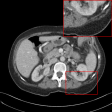

Figure 4: Qualitative results of our method and other baselines on Mayo Clinic Low Dose CT dataset. (a) Real low-dose. (b)-(f) Results of each methods. (g) Real normal-dose. As shown in the highlighted red box, the reconstructed image by our method has few noise and artifacts. The display window is [160,240]160240[160,240] HU.

Table 2: The average PSNR and SSIM results of different methods on Mayo Clinic Low Dose CT dataset. Our results are marked in bold.

Denoising on Low-Dose CT

Since Computed Tomography (CT) helps to diagnose abnormalities of organs, CT is widely used in medical analysis. Reducing the radiation dose in order to decrease health risks causes noise and artifacts in the reconstructed images. Like the real-world noise, the noise distributions of the reconstructed image are difficult to model analytically. Therefore, we adopt a CT dataset authorized by Mayo Clinic [Moen etย al.(2021)Moen, Chen, Holmesย III, Duan, Yu, Yu, Leng, Fletcher, and McCollough] to evaluate the generalization ability of our method on real-world noise. Mayo Clinic dataset consists of paired normal-dose and lose-dose CT images for each patient. The Normal-Dose CT (NDCT) and the Low-Dose CT (LDCT) images correspond to clean and noisy images, respectively. For the training, we obtain 2,850 images in 512ร—512512512512\times 512 resolution from 20 different patients. We construct 1,422 LDCT images from randomly selected 10 patients as a noise set and 1,428 NDCT images from the remaining patients as a clean set for unpaired training. For the test, we obtain 865 images from 5 different patients. As shown in Table 2, our method achieves the best and the second-best performance in PSNR and SSIM, respectively. Note that our model trained on the unpaired dataset outperforms the RED-CNN trained on the paired dataset in PSNR. It indicates that our method can be more practical in medical analysis where obtaining paired datasets is challenging. We also compare the qualitative results with other baselines. As shown in Figure 4, other methods tend to generate artifacts or lose details. On the other hand, our method shows a reasonable balance between noise removal and image quality. More qualitative results are provided in the supplementary material.